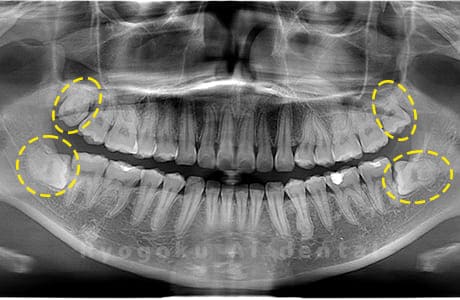

斜めに生えている親知らず

親知らずが斜めに生えて隣の歯にぶつかって圧迫してしまうタイプです。

このタイプが最も多いです。このタイプは虫歯になりやすいだけでなく、隣の歯を圧迫し、咬み合わせや歯並びに影響が出る場合もあるので抜歯をおすすめします。